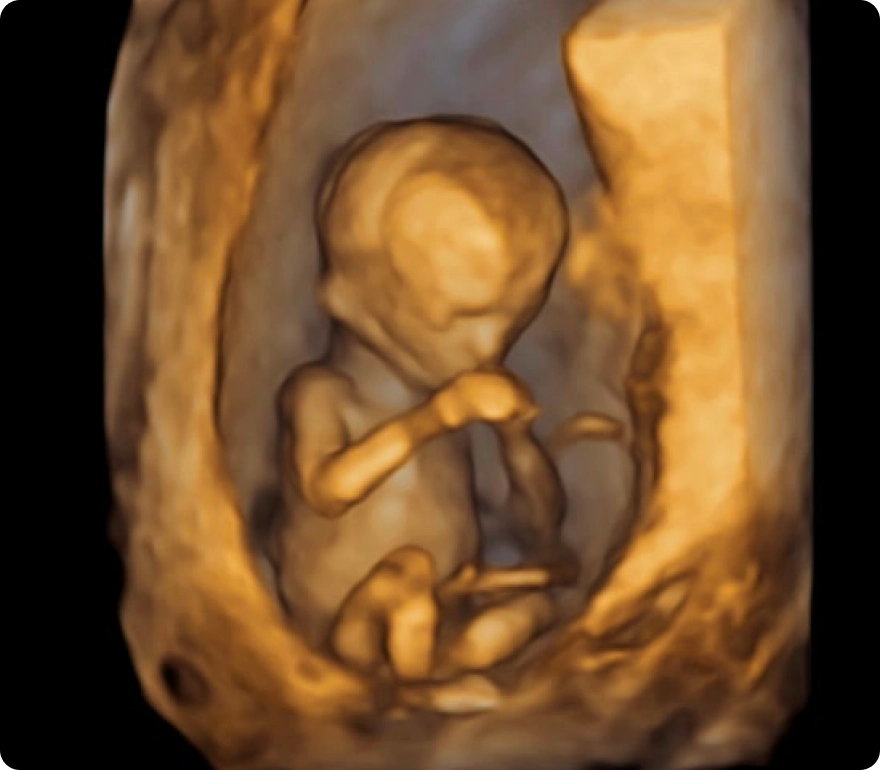

Our advanced HD ultrasounds offer breathtaking clarity and detail, allowing you to see your baby like never before. Every image and movement becomes a memory—one you can share and treasure for a lifetime.

Our state-of-the-art ultrasound technology gives you a front-row seat to your baby’s world. From tiny yawns and gentle stretches to blinking, swallowing, and little finger wiggles, our 3D, 4D, and HD ultrasounds capture these once-in-a-lifetime moments with stunning clarity and detail.

Advanced technology with stunning clarity, color, and detail—offering the most realistic, lifelike view of your baby before birth.